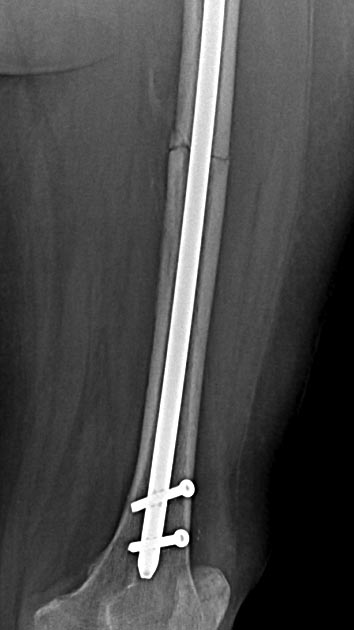

Слева к коротктй ножке просится ретроградный гвоздь с рассерливанием ( мерил- помещается.), или стандарная ножка с уральским опорным гвоздем ( методика при перипротезныз переломах Челнокова и К) возможно-ли ?

О коротких ножках впечатления скорее положительные, большей частью выживают нормально,если правильно выбирать показания, правда сроки наблюдения пока небольшие, чаще всего лет 5. В этом случае я бы не рискнул - конечность была неопорная 5 мес, метафиз явно пострадал, кроме того непонятно, что осталось от шейки.

"Уральский опорный гвоздь" сделать можно, но нужно ли? Таким образом вы получите ту же самую ревизионную ногу со всеми ее "прелестями".